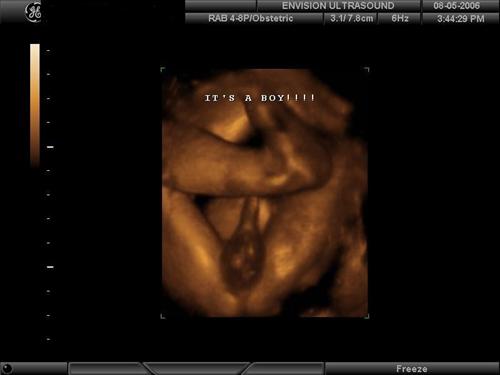

Ok you guys asked for it  We went to Envision Ultrasound in Brooklyn, per the recommendations of so many ladies on this board. I had checked with my doctor and she totally approved us having this done. If anyone has any questions and /or would like more details about Envision, I would be happy to give you my insight into the experience.. they were wonderful. Here are some of my favorite pics of our little monkey ... Favorite face shots:

AND here it is.... confirmation that our baby is, in fact, ALL BOY! X-rated shot -- warning!!

(no he is definitely not a shy baby!)

DH loved that one